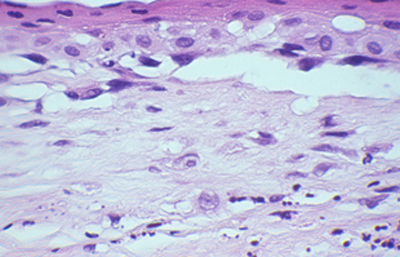

Cuando el examen patológico se realiza en cortes de tejido corneal procesados en parafina, (biopsias y discos de córnea de queratoplastias) las coloraciones que empleamos usualmente son la coloración de Hematoxilina-Eosina (Figura 49), el Blanco de Calcofluor. (Figura 50), la de PAS (Figura 51 y 52). De nuevo, la consideración de que una infección corneal puede ser causada por Acantamoebas es la condición indispensable en el diagnóstico diferencial para llegar a su diagnóstico

Fig. 49 H-E, Original x160